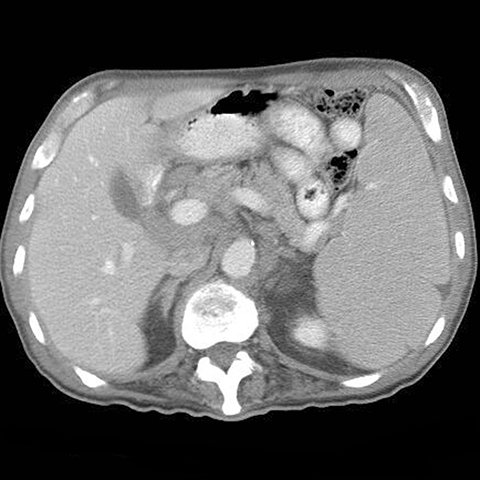

26-year old presents with night sweats and fever. [1 of 2]